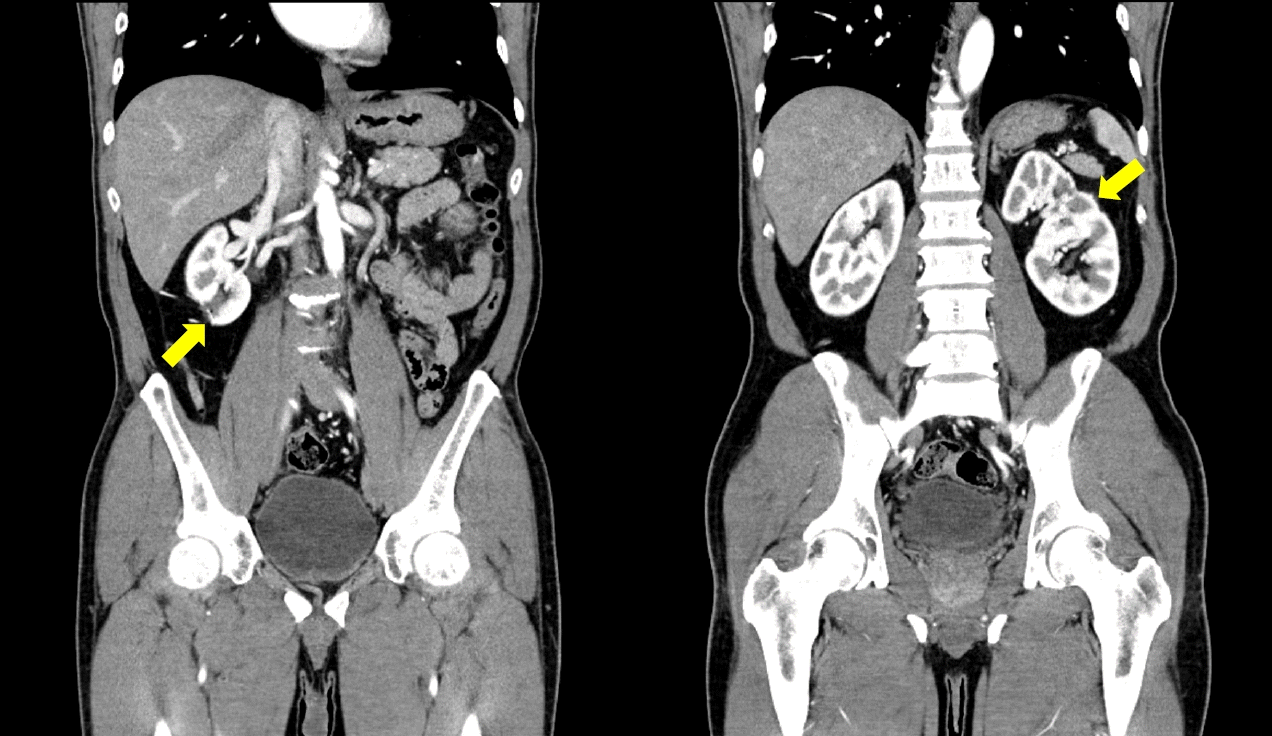

A 52-year-old man presents to the outpatient urology department with an incidentally discovered bilateral kidney mass by ultrasound. On the abdominal computed tomography (CT), the masses measured 1.5 cm on the right and 2.0 cm on the left. The RENAL (radius, exophytic/endophytic, nearness to collecting system or sinus, anterior/posterior, and location relative to polar lines) nephrometry score was 5 for both sides the PADUA (preoperative aspects and dimensions used for an anatomical) score was 7 for the left and 8 for the right sides (Fig. 1). The patient had no previous history of surgery or trauma and no history of comorbidities or medications. Preoperatively, serum creatinine and estimated glomerular filtration rate (eGFR) were 0.81 mg/dL and 86.7 mL/min/1.73 m2, respectively. All other preoperative laboratory findings were within normal limits. His body mass index was 24.3 kg/m2. Given the relatively small size of the masses, a preoperative biopsy was not performed.

Fig. 1.

The coronary images on preoperative computed tomography show (A) a 1.5-cm right and (B) a 2.0-cm left endophytic mass (arrows).